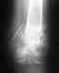

Открытый перелом голени(посередине) с осколком и смещением

13 сентября я попал в ДТП.меня превезли в ЦРБ, прооперировали( зашили рану, выставили кость ровно и положили на вытяжку)21 сентября перевели в другую больницу. 25 сентября прооперировали и поставили стержневой аппарат.

Cейчас я уже нормально хожу. месяца 1,5 назад ездил на консультацию и делал снимок. врач сказал что срастается нормально, но пока ещё достаточно отчётливо виден просвет и сказал чтобы ногу я сильно не нагружал(ходил 2 - 3 километра в день не больше, а то может образоваться ложный сустав).Стержневой аппарат мне сказали будут снимать 1 марта.У меня вопрос такой - когда мне можно будет ходить больше и на сколько больше?